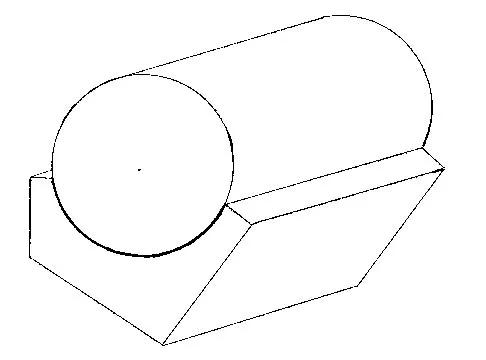

Consider the theoretic articulation shown in Figure 11 as femoral and tibial components of a total knee prosthesis in which the components fit like a "roller in trough." Which of the following best describes the articulation?

Explanation